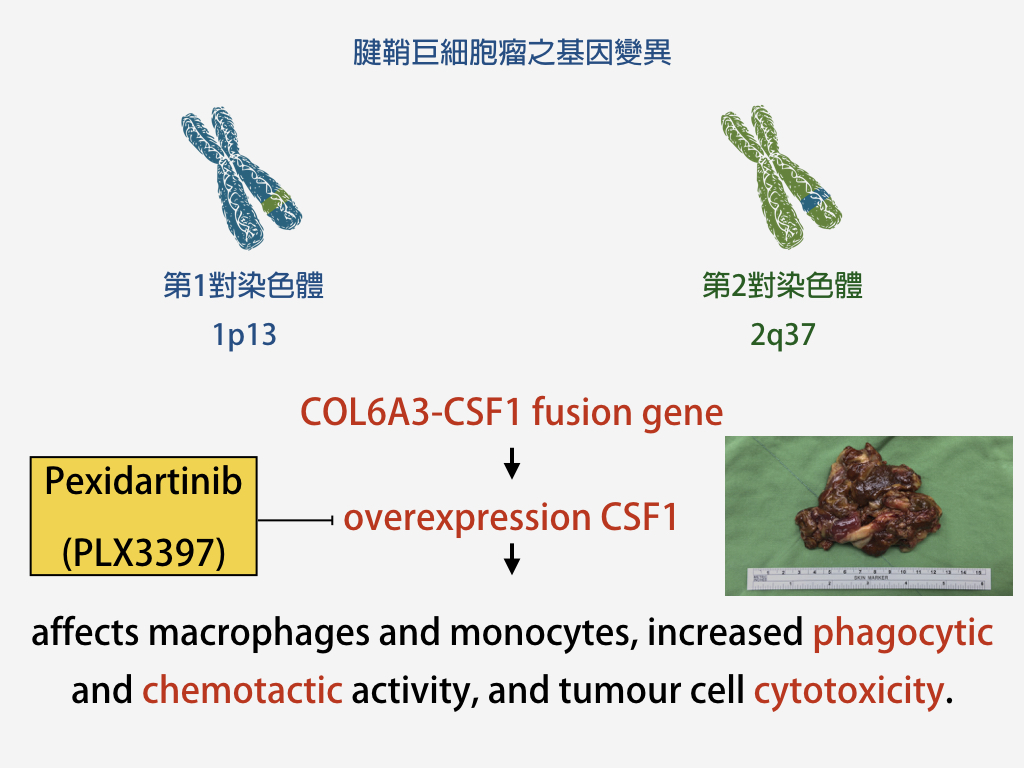

腱鞘巨細胞瘤(或又稱色素絨毛結節性滑膜炎)發生的病因,目前仍尚未完全清楚。在過去許多的研究認為,可能與慢性發炎、受傷與脂肪代謝異常有關。而在2007與2008時,分別於美國Stanford 大學(*)與瑞典 Lund 大學(**)分別提出腱鞘巨細胞瘤與COL6A3和CSF1這兩個基因突變之關聯。但就目前的研究,大約僅有20%之腱鞘巨細胞瘤的形成與這兩個基因有相關。

另外必須一提的,在目前的藥物中,有一個可能成為未來治療腱鞘巨細胞瘤(色素絨毛結節性滑膜炎)最重要的關鍵,便是 Pexidartinib (PLX3397) ,CSF-1 receptor inhibitor。國外醫學團隊分別於2015年在 新格蘭醫學期刊 (NEJM)(***)與 刺絡針腫瘤期刊(Lancet Oncology)(***)中,發表了使用 PLX3397 來治療色素絨毛結節性滑膜炎成果,相當令我們震撼!我們台灣目前(2017.4.3)尚未引進此藥物,但希望在2017年底前,我們可以見到這個藥物的引入,相信可以幫助許多需要的病患!